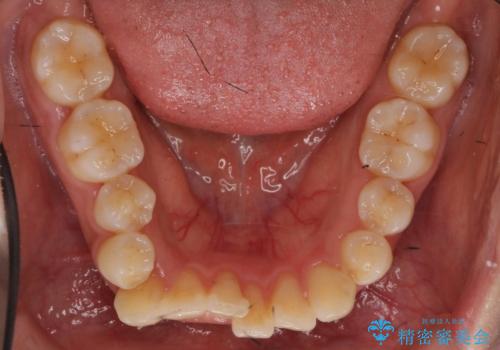

右上の半分埋まっている犬歯を抜歯し、残り上下左右3本抜歯してワイヤー矯正を行いました。

前歯が斜めになっているのもだいぶ改善しました。